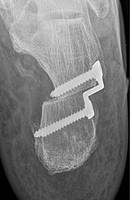

Abb.4: Gelenkerhaltende Korrektur eine Plattfußes durch Verschiebung des Fersenbeins (Calcaneusverschiebeosteotomie, Medial Slide Osteotomy), Fixierung des Knochens mir einer winkelstabilen Platte

Führen diese Maßnahmen nicht zum Erfolg, kommen operative Maßnahmen in Betracht. Diese sind im Stadium I die Entfernung oder das Spalten des Sehnenleitgewebes, im Stadium II wird durch eine Fersenbein Umstellung die mechanische Belastungsachse wieder hergestellt. Das Fersenbein wird bei diesem Eingriff um bis zu 15 mm verschoben und mit einer Spezialplatte fixiert (Calcaneusverschiebe osteotomie, Medial slide Osteotomy). Es handelt sich um verlässliche Operationen um die Fehlstellung dauerhaft zu beheben. Die Verschiebung führt zu einer Entlastung der tragenden Sehne und zu einer Korrektur der Rückfußfehlstellung. In gleicher Sitzung werden die überdehnten Weichteile an der Fußinnenseite gerafft und ggf. ein Sehnentransfer durchgeführt. Bei jungen Erwachsenen kann die Rekonstruktion auch durch eine Verlängerung des Fersenbeins (Evans Osteotomie) erfolgen. Die Fixierung erfolgt mit einer Schraube. Bei jugendlichen im Alter zwischen 10 und 15 Jahren ist häufig eine Aufrichtung ohne eine Knochendurchtrennung möglich. Das Verfahren wird als Arthrorise bezeichnet und kann minimalinvasiv durchgeführt werden. Leider quälen sich viele Patienten zu lange und kommen erst dann in die Fußsprechstunde wenn eine deutliche Bewegungseinschränkung und Arthrose im Mittel- und Rückfuß bereits eingetreten ist. In diesen Fällen (Stadium III und IV) können wir nur noch mit einer korrigierenden Arthrodese (Gelenkfusion) helfen. Die Patienten profitieren auch von diesem Eingriff insbesondere bzgl. der Schmerzsymptomatik erheblich, jedoch kann eine leichte Einschränkung beim Gehen verbleiben. Ein spezielles orthopädisches Schuhwerk ist in der Regel nicht notwendig.